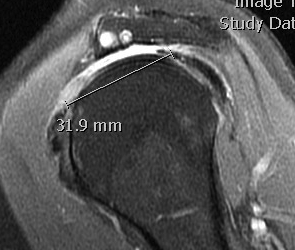

Small full thickness rotator cuff tear of supraspinatus - retracted to footprint

Large full thickness tear of supraspinatus and infraspinatus tendon - retracted to midhumeral head

Massive rotator cuff tear of the supraspinatus and infraspinatus tendon - retracted to glenoid